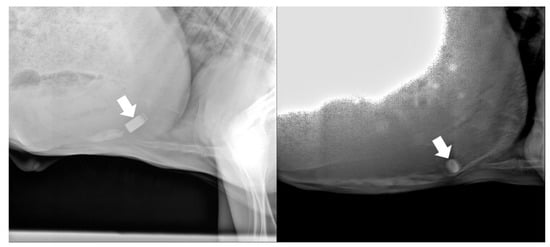

3.1. Retention and Location of the Biosensor